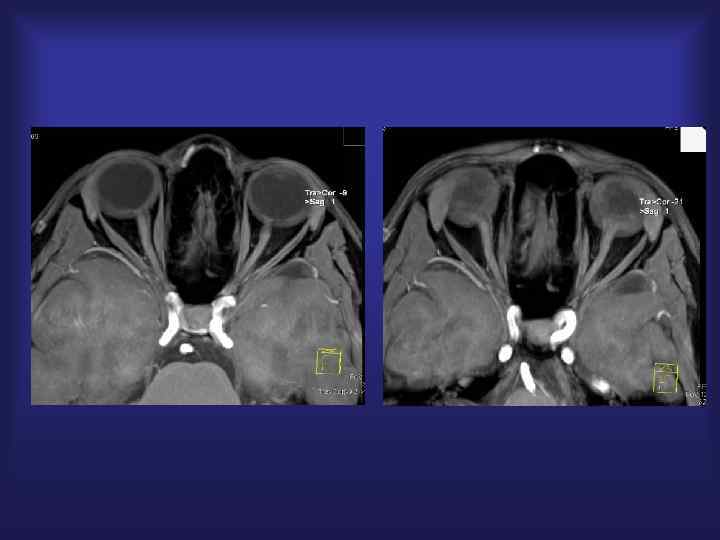

Парасагиттальная менингиома Венография - 2 D TOF

2 D TOF +Gd

Парасагиттальная менингиома СКТ Костная деструкция

СКТ 3 D обработка

СКТ : костные ориентиры

Менингиома ( парасагиттальная) СКТ-Аг Окклюзия ВСС